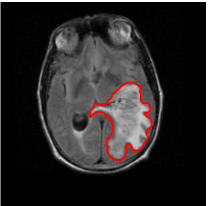

The relevance of tumor shape in characterizing tumor heterogeneity is linked to its growth process. Intrinsic brain tumors tend to evolve along tracts of white matter, altering the tracts in complex ways that include infiltration, displacement and disruption (Goldberg-Zimring et al., 2005). It is conceivable that new insight into patterns of tumor growth and invasion in the brain can be obtained through a better understanding of the shape and evolution of the tumor. Tumor shape is significantly influenced by the location in the brain and other anatomical constraints—in some places it might infiltrate and in others displace the fiber tracts. Irregular or spiculated shapes suggest an anisotropic structure of the underlying white matter; spherical or regular shapes imply a lack of structural or anatomical restrictions. The size of the tumor evidently affects its shape, especially in the presence of anatomical restrictions. It is reasonable to theorize that a better understanding of the relationship between the tumor’s shape and size, and histopathological factors related to the brain tumor would enhance the understanding of the tumor’s biological growth process; this would not only enable better prognosis but also potentially predict the likelihood of therapeutic success. For example, Figure 1 of our motivating dataset shows two semi-automated segmentations of T2-weighted fluid-attenuated inversion recovery (FLAIR) brain-axial MRI of patients diagnosed with glioblastoma multiforme (GBM), also known as grade IV glioma, with survival times of longer than 50 months (left) and shorter than one month (right), respectively. The tumor shape for the patient with longer survival appears to be more regular or spherical than the irregular one corresponding to the patient with a short survival; the tumor sizes appear to be quite different as well. Evidently, the tumor locations for the two patients are different, which influences both size and shape.